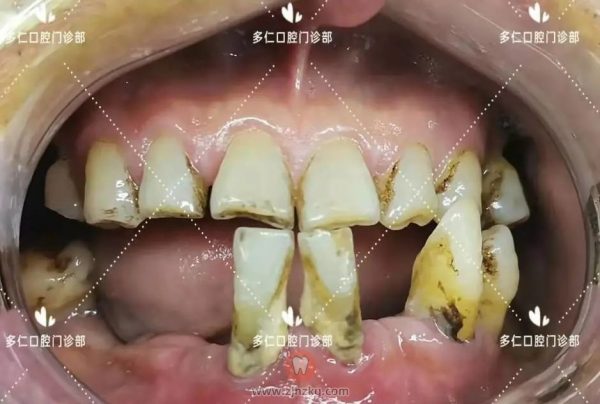

术前口内照